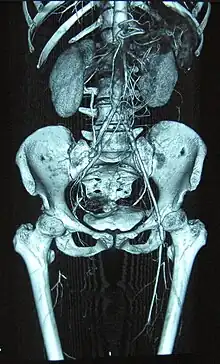

| Complete occlusion of the right and stenosis of the left femoral artery as seen in a case of thromboangiitis obliterans | |

Angiograms of the upper and lower extremities can be helpful in making the diagnosis of Buerger's disease. In the proper clinical setting, certain angiographic findings are diagnostic of Buerger's. These findings include a "corkscrew" appearance of arteries that result from vascular damage, particularly the arteries in the region of the wrists and ankles. Collateral circulation gives "tree root" or "spider leg" appearance.[1] Angiograms may also show occlusions (blockages) or stenosis (narrowings) in multiple areas of both the arms and legs. Distal plethysmography also yields useful information about circulatory status in digits. To rule out other forms of vasculitis (by excluding involvement of vascular regions atypical for Buerger's), it is sometimes necessary to perform angiograms of other body regions (e.g., a mesenteric angiogram).